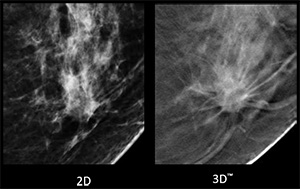

腫瘤(しこり)のある方では、辺縁がくっきり見えるため、良悪性の区別が付きやすいです。